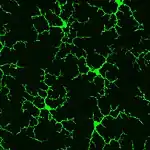

Microglia

.jpg.webp)

Microglia are the tissue-resident phagocytes of the central nervous system. CSF1R signaling promotes migration of primitive microglia precursor cells from the embryonic yolk sac to the developing brain prior to formation of the blood-brain-barrier. In perinatal development, microglia are instrumental in synaptic pruning, a process in which microglia phagocytose weak and inactive synapses via binding of microglial complement receptor 3 (CR3) (complex of CD11b and CD18) to synapse-bound iC3b. Csf1r loss-of-function inhibits synaptic pruning and leads to excessive non-functional synapses in the brain. In adulthood, CSF1R is required for the proliferation and survival of microglia.[12] Inhibition of CSF1R signaling in adulthood causes near-complete (>99%) depletion (death) of brain microglia, however reversal of CSF1R inhibition stimulates remaining microglia to proliferate and repopulate microglia-free niches in the brain.[13] Production of CSF1R ligands CSF-1 and IL-34 is increased in the brain following injury or viral infection, which directs microglia to proliferate and execute immune responses.[12]